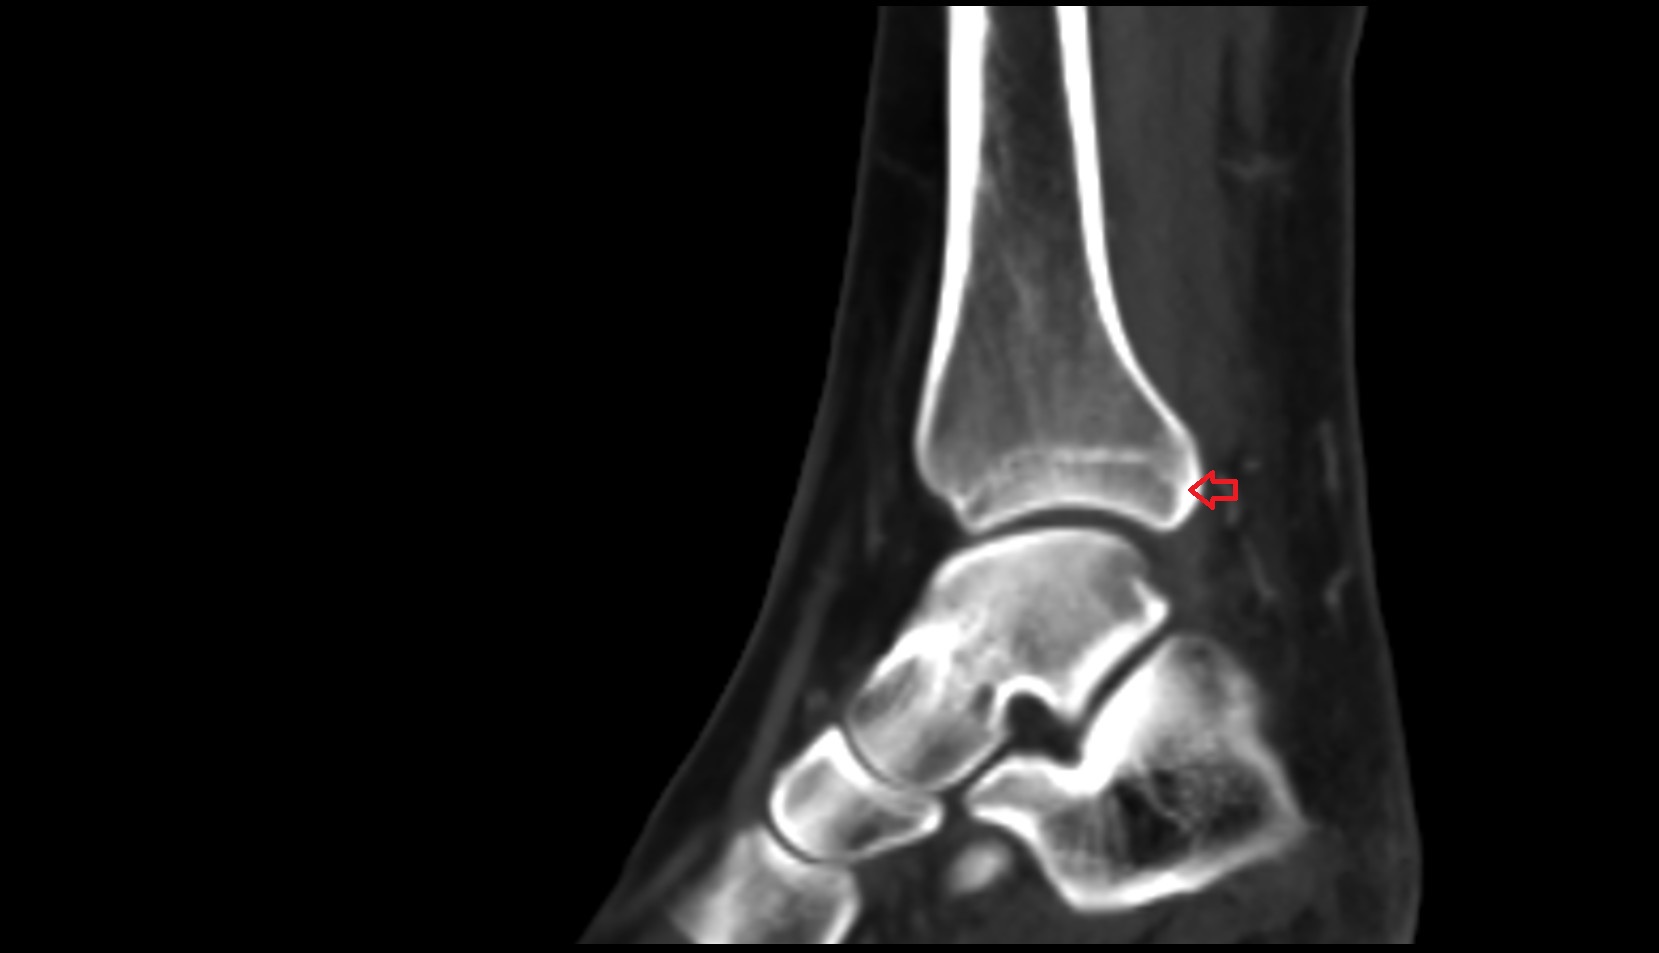

- Talus

- Body of talus

- Medial malleolus

- Lateral malleolus

- Ankle joint

- Talocalcaneal joint